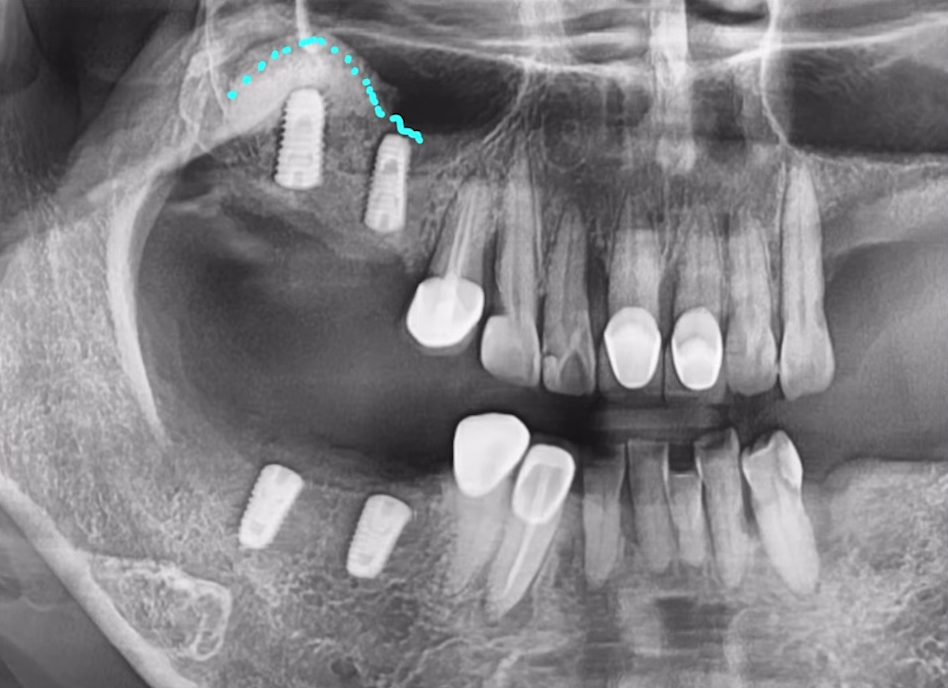

61세 남성 환자분이셨고

임플란트를 심기에는 전체적으로 염증이 많이 퍼져 있는 상태였습니다.

하여 발치를 결정한 치아들은 순차적으로 발치를 다 해드렸고,

염증 제거와 잇몸뼈 회복이 우선이었기에

뼈가 어느 정도 아물 때까지 3개월 정도 기다렸습니다.

그런데 사실상 남아 있는 뼈들도 부족한 상태고,

임플란트 심기에는 상악동 뼈도 굉장히 얇은 상태입니다.

이런 상태에서는 무리하게 식립하다가

임플란트가 상악동에 빠지는 사고가 발생할 수도 있습니다.

당일에 뼈이식과 상악동 뼈 이식을 해드려 뼈를 충분히 보강한 후, 동시 식립까지 진행했습니다.

상악동에 뼈 잘 이식된 것 보시이죠?

CT 사진으로 잘 식립된 것까지 체크해 드린 후 다음 날 반대편까지 안전하게 심어드렸습니다.